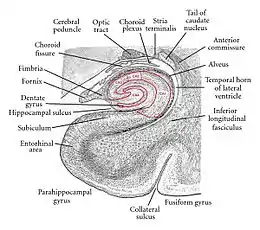

Hippocampus

The hippocampus is involved with various processes relating to cognition and is one of the best understood and heavily involved limbic interacting structure.

Spatial memory

The first and most widely researched area concerns memory, particularly spatial memory. Spatial memory was found to have many sub-regions in the hippocampus, such as the dentate gyrus (DG) in the dorsal hippocampus, the left hippocampus, and the parahippocampal region. The dorsal hippocampus was found to be an important component for the generation of new neurons, called adult-born granules (GC), in adolescence and adulthood.[16] These new neurons contribute to pattern separation in spatial memory, increasing the firing in cell networks, and overall causing stronger memory formations. This is thought to integrate spatial and episodic memories with the limbic system via a feedback loop that provides emotional context of a particular sensory input.[17]

While the dorsal hippocampus is involved in spatial memory formation, the left hippocampus is a participant in the recall of these spatial memories. Eichenbaum[18] and his team found, when studying the hippocampal lesions in rats, that the left hippocampus is "critical for effectively combining the 'what', 'when', and 'where' qualities of each experience to compose the retrieved memory". This makes the left hippocampus a key component in the retrieval of spatial memory. However, Spreng[19] found that the left hippocampus is a general concentrated region for binding together bits and pieces of memory composed not only by the hippocampus, but also by other areas of the brain to be recalled at a later time. Eichenbaum's research in 2007 also demonstrates that the parahippocampal area of the hippocampus is another specialized region for the retrieval of memories just like the left hippocampus.

Learning

The hippocampus, over the decades, has also been found to have a huge impact in learning. Curlik and Shors[20] examined the effects of neurogenesis in the hippocampus and its effects on learning. This researcher and his team employed many different types of mental and physical training on their subjects, and found that the hippocampus is highly responsive to these latter tasks. Thus, they discovered an upsurge of new neurons and neural circuits in the hippocampus as a result of the training, causing an overall improvement in the learning of the task. This neurogenesis contributes to the creation of adult-born granules cells (GC), cells also described by Eichenbaum[18] in his own research on neurogenesis and its contributions to learning. The creation of these cells exhibited "enhanced excitability" in the dentate gyrus (DG) of the dorsal hippocampus, impacting the hippocampus and its contribution to the learning process.[18]

Hippocampus damage

Damage related to the hippocampal region of the brain has reported vast effects on overall cognitive functioning, particularly memory such as spatial memory. As previously mentioned, spatial memory is a cognitive function greatly intertwined with the hippocampus. While damage to the hippocampus may be a result of a brain injury or other injuries of that sort, researchers particularly investigated the effects that high emotional arousal and certain types of drugs had on the recall ability in this specific memory type. In particular, in a study performed by Parkard,[21] rats were given the task of correctly making their way through a maze. In the first condition, rats were stressed by shock or restraint which caused a high emotional arousal. When completing the maze task, these rats had an impaired effect on their hippocampal-dependent memory when compared to the control group. Then, in a second condition, a group of rats were injected with anxiogenic drugs. Like the former these results reported similar outcomes, in that hippocampal-memory was also impaired. Studies such as these reinforce the impact that the hippocampus has on memory processing, in particular the recall function of spatial memory. Furthermore, impairment to the hippocampus can occur from prolonged exposure to stress hormones such as glucocorticoids (GCs), which target the hippocampus and cause disruption in explicit memory.[22]

In an attempt to curtail life-threatening epileptic seizures, 27-year-old Henry Gustav Molaison underwent bilateral removal of almost all of his hippocampus in 1953. Over the course of fifty years he participated in thousands of tests and research projects that provided specific information on exactly what he had lost. Semantic and episodic events faded within minutes, having never reached his long-term memory, yet emotions, unconnected from the details of causation, were often retained. Dr. Suzanne Corkin, who worked with him for 46 years until his death, described the contribution of this tragic "experiment" in her 2013 book.[23]